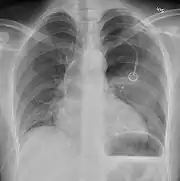

Anteroposterior inspired X-ray, showing subtle left-sided pneumothorax caused by port insertion

It is not unusual for the mediastinum (the structure between the lungs that contains the heart, great blood vessels, and large airways) to be shifted away from the affected lung due to the pressure differences. This is not equivalent to a tension pneumothorax, which is determined mainly by the constellation of symptoms, hypoxia, and shock.[13]

The size of the pneumothorax (i.e. the volume of air in the pleural space) can be determined with a reasonable degree of accuracy by measuring the distance between the chest wall and the lung. This is relevant to treatment, as smaller pneumothoraces may be managed differently. An air rim of 2 cm means that the pneumothorax occupies about 50% of the hemithorax.[15] British professional guidelines have traditionally stated that the measurement should be performed at the level of the hilum (where blood vessels and airways enter the lung) with 2 cm as the cutoff,[15] while American guidelines state that the measurement should be done at the apex (top) of the lung with 3 cm differentiating between a "small" and a "large" pneumothorax.[33] The latter method may overestimate the size of a pneumothorax if it is located mainly at the apex, which is a common occurrence.[15] The various methods correlate poorly but are the best easily available ways of estimating pneumothorax size.[15][19] CT scanning (see below) can provide a more accurate determination of the size of the pneumothorax, but its routine use in this setting is not recommended.[33]

Not all pneumothoraces are uniform; some only form a pocket of air in a particular place in the chest.[15] Small amounts of fluid may be noted on the chest X-ray (hydropneumothorax); this may be blood (hemopneumothorax).[13] In some cases, the only significant abnormality may be the "deep sulcus sign", in which the normally small space between the chest wall and the diaphragm appears enlarged due to the abnormal presence of fluid.[16]